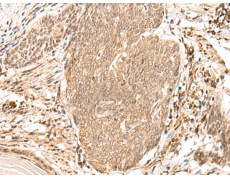

IHC positive control: |

Human esophagus cancer and Human thyroid cancer |

IHC Recommend dilution: |

50-300 |